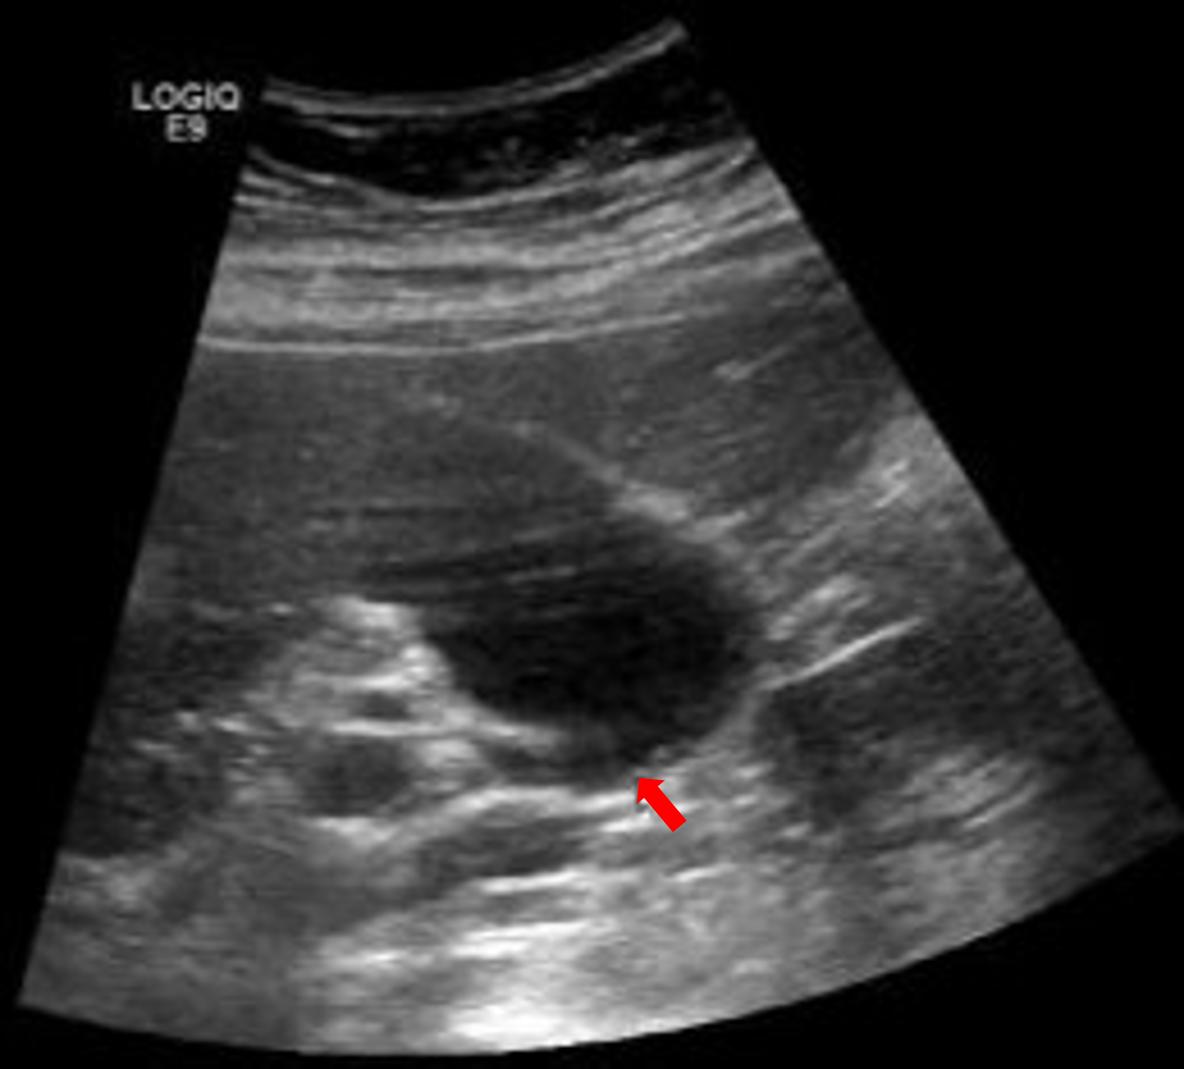

图三,空腹患者的胆囊,胆囊充盈良好,内壁显示很清楚,即使这种不到2mm的小结石,仔细观察也是可以发现的。